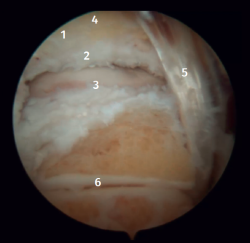

Anatomía artroscópica del complejo medial

Mediante la artroscopia podremos ver las fibras profundas del ligamento deltoideo, que es la porción intraarticular del ligamento. Medial y proximalmente a la punta del maléolo ya tenemos la inserción de la capa profunda del ligamento deltoideo. Si no hay lesión, veremos la porción anterior de las fibras tibioastragalinas profundas. Cuando existe una lesión de estas, podemos visualizar la porción intermedia y posterior. Las bandas superficiales, por su ubicación más externa, no son visibles mediante artroscopia, a no ser que no exista una lesión de las profundas (Figura 5).

Figura 5. A: visión anterior del receso medial del tobillo; B: con el palpador tensamos las fibras del ligamento tibiotalar profundo.